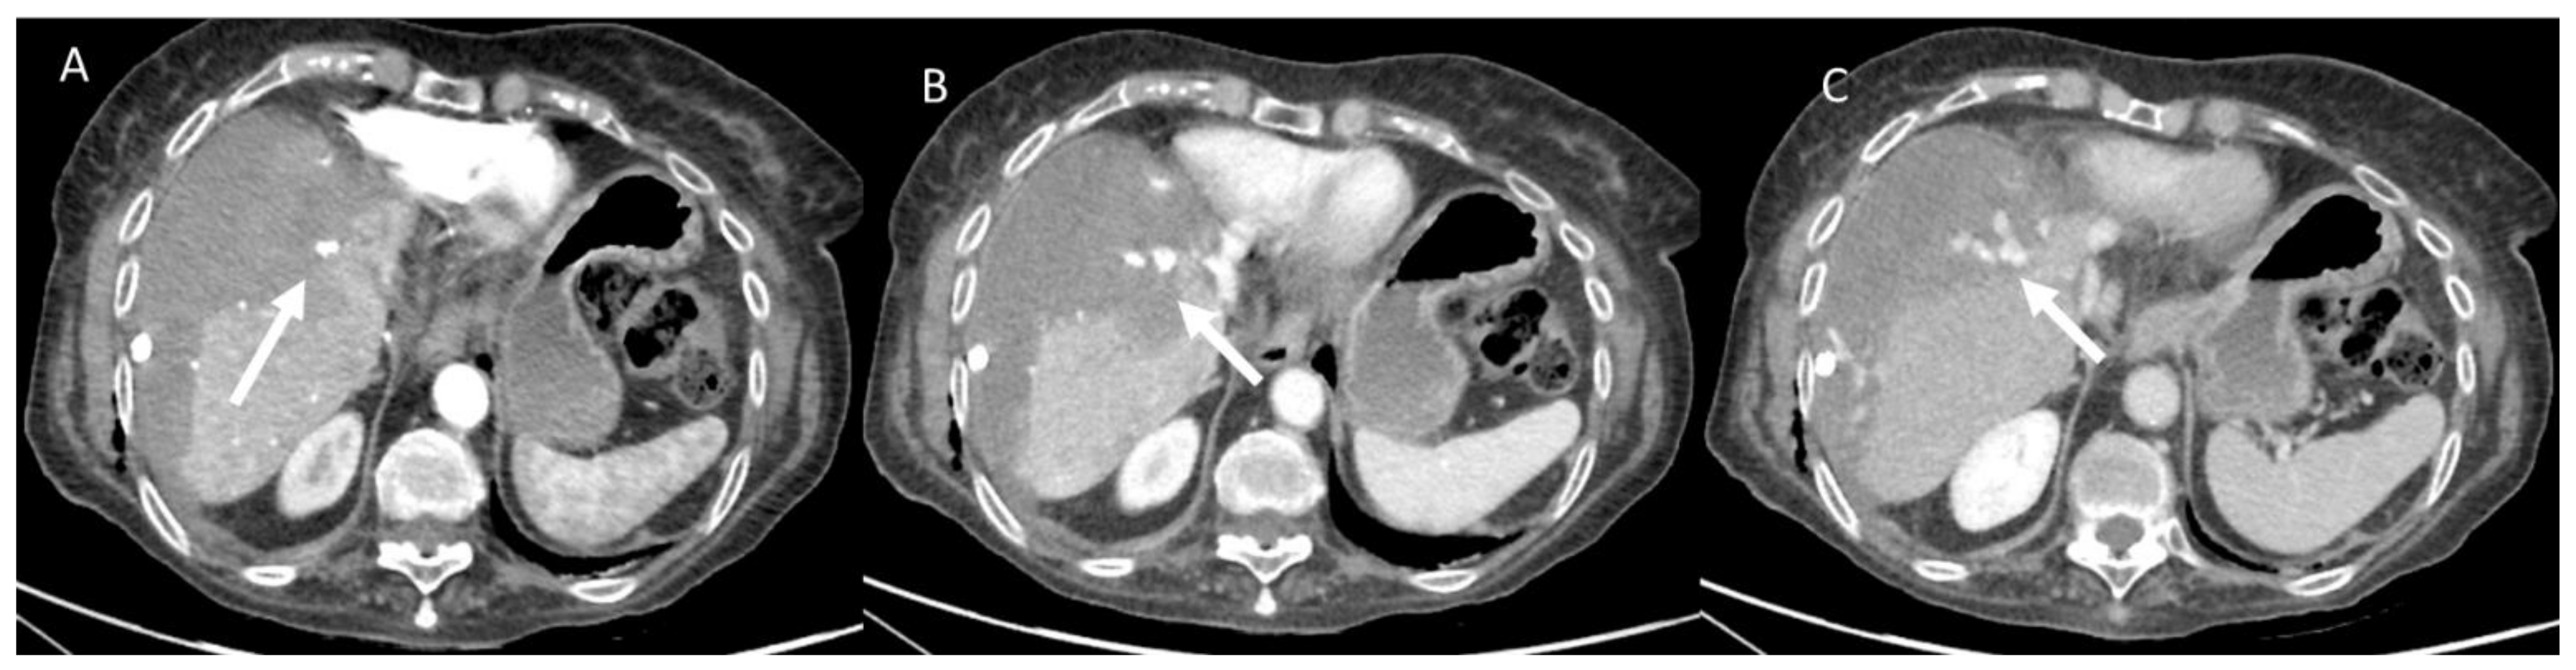

- Granata, V.; Grassi, R.; Fusco, R.; Belli, A.; Cutolo, C.; Pradella, S.; Grazzini, G.; La Porta, M.; Brunese, M.C.; De Muzio, F.; et al. Diagnostic evaluation and ablation treatments assessment in hepatocellular carcinoma. Infect. Agents Cancer 2021, 16, 53. [Google Scholar] [CrossRef] [PubMed]

- Izzo, F.; Granata, V.; Grassi, R.; Fusco, R.; Palaia, R.; Delrio, P.; Carrafiello, G.; Azoulay, D.; Petrillo, A.; Curley, S.A. Radiofrequency Ablation and Microwave Ablation in Liver Tumors: An Update. Oncologist 2019, 24, e990–e1005. [Google Scholar] [CrossRef] [Green Version]

- Granata, V.; Grassi, R.; Fusco, R.; Setola, S.; Belli, A.; Piccirillo, M.; Pradella, S.; Giordano, M.; Cappabianca, S.; Brunese, L.; et al. Abbreviated MRI Protocol for the Assessment of Ablated Area in HCC Patients. Int. J. Environ. Res. Public Health 2021, 18, 3598. [Google Scholar] [CrossRef]